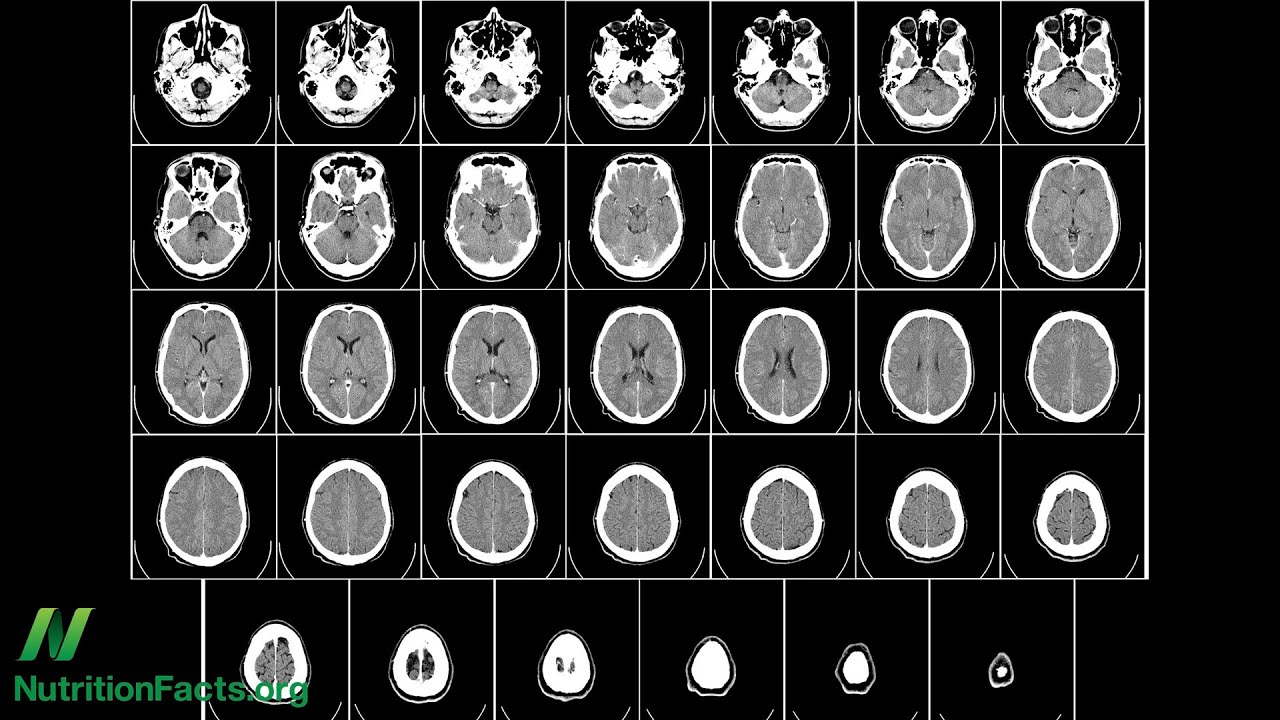

Folaat draagt bij aan de ontwikkeling van het centraal zenuwstelsel. Een deficiëntie bij de moeder wordt gekoppeld aan neurale buisdefecten, vertraagde intellectuele ontwikkeling en andere mentale stoornissen bij het nageslacht.

Een verlaagde folaatstatus van de moeder tijdens de vroege zwangerschap wordt geassocieerd met hyperactiviteit in de kindertijd en problemen met leeftijdsgenoten,

Als de moeder tijdens de zwangerschap een vitamine B12 tekort heeft kan dit gevolgen hebben voor de baby ( ontwikkelingsachterstand en cerebrale atrofie). Dit kan wel worden teruggedraaid.